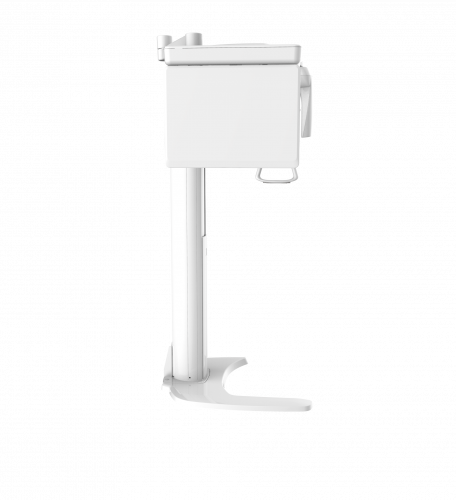

| TYPE | TOP VIEW | FRONT VIEW |

|---|---|---|

|

PaX-i (Pano) |

|

|

|

PaX-i SC (Pano/Scan Ceph) |

|

|